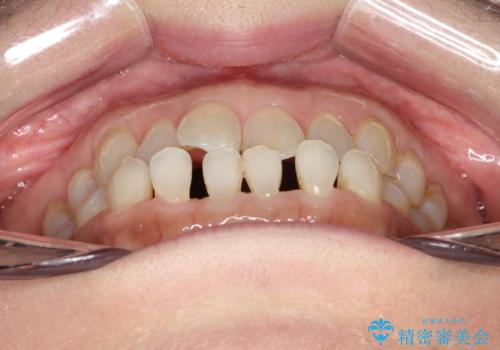

前歯の隙間 インビザラインによる目立たない成人矯正

- 前歯の隙間を気にされて来院されました。

インビザラインにて、目立たずに矯正治療を行うこととしました。

歯と歯の間にある隙間を閉じるのは、インビザラインでもしっかり治療できます。